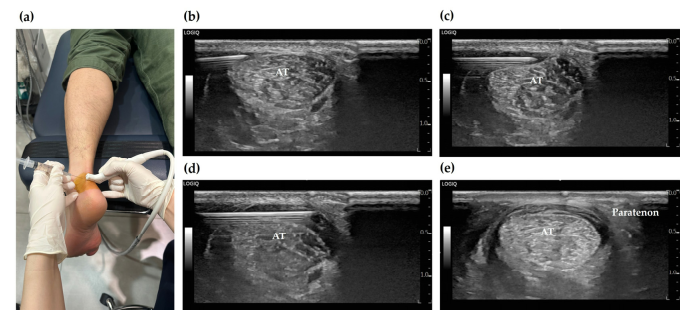

오래된 아킬레스건병증은 대부분 힘줄 주변에 있는 건 주위 조직(paratenon)에 염증이 있습니다. 이 조직에 통증을 느끼는 수용체와 혈관이 풍부해서 심한 통증의 원인이 됩니다.

발목 외측의 곤륜혈(崑崙, BL60)에서 염증이 있는 건 주위 조직에 정밀하게 염증을 완화하는 약침을 주사합니다. 환자 상태에 따라 봉약침, 태반 자하거 약침, PDRN 연아약침 등 소염 진통 성분의 약침 약물이 들어갑니다. > 2단계: 근막 유착 풀기 > > 근막통증 증후군 치료